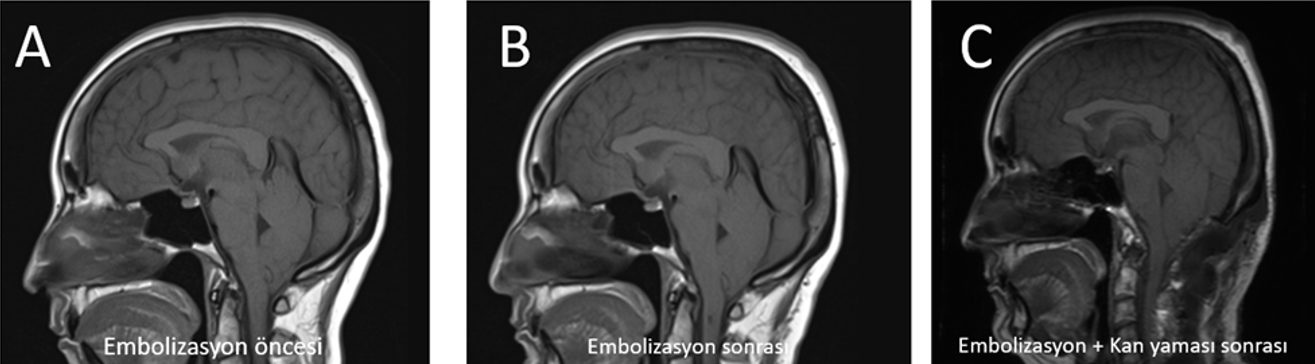

Tip 3 CVF: Embolizasyon ve Rebound

Vakalar 6 ve 7 (aynı hasta, iki yatış) CVF yönetiminin iki kritik ilkesini örneklemektedir. İlk yatışta dış merkezlerdeki EKY denemelerine yanıtsız Bern 9 olgu, BT miyelografi ile D2 hemiazigos CVF’si olarak tanımlanarak başarılı DSA embolizasyonu (Onyx) ile tedavi edildi; Pre- ve post-embolizasyon MRG görüntüleri Şekil 6’da sunulmaktadır.17,18 İkinci yatışta embolizasyon sonrası rebound intrakraniyal hipertansiyon, sekonder Chiari morfolojisi ve komünikan hidrosefali gelişti; posterior fossa dekompresyonu ve V/P şant gereksinimi oldu. Bu komplikasyon CVF tedavisi sonrasında aktif radyolojik izlemin kritik önemini vurgulamaktadır.